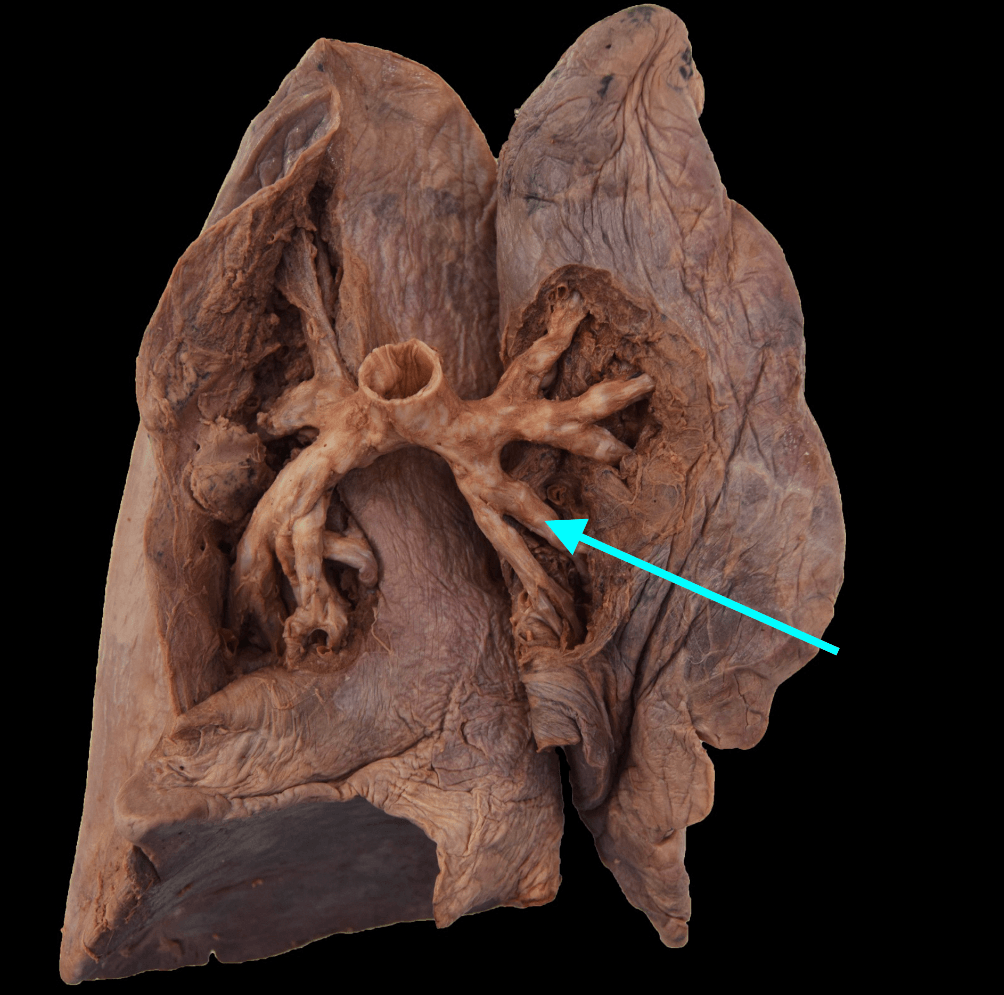

The structure indicated by the blue arrow

What is the superior lingular tertiary bronchus of the left superior lobe?